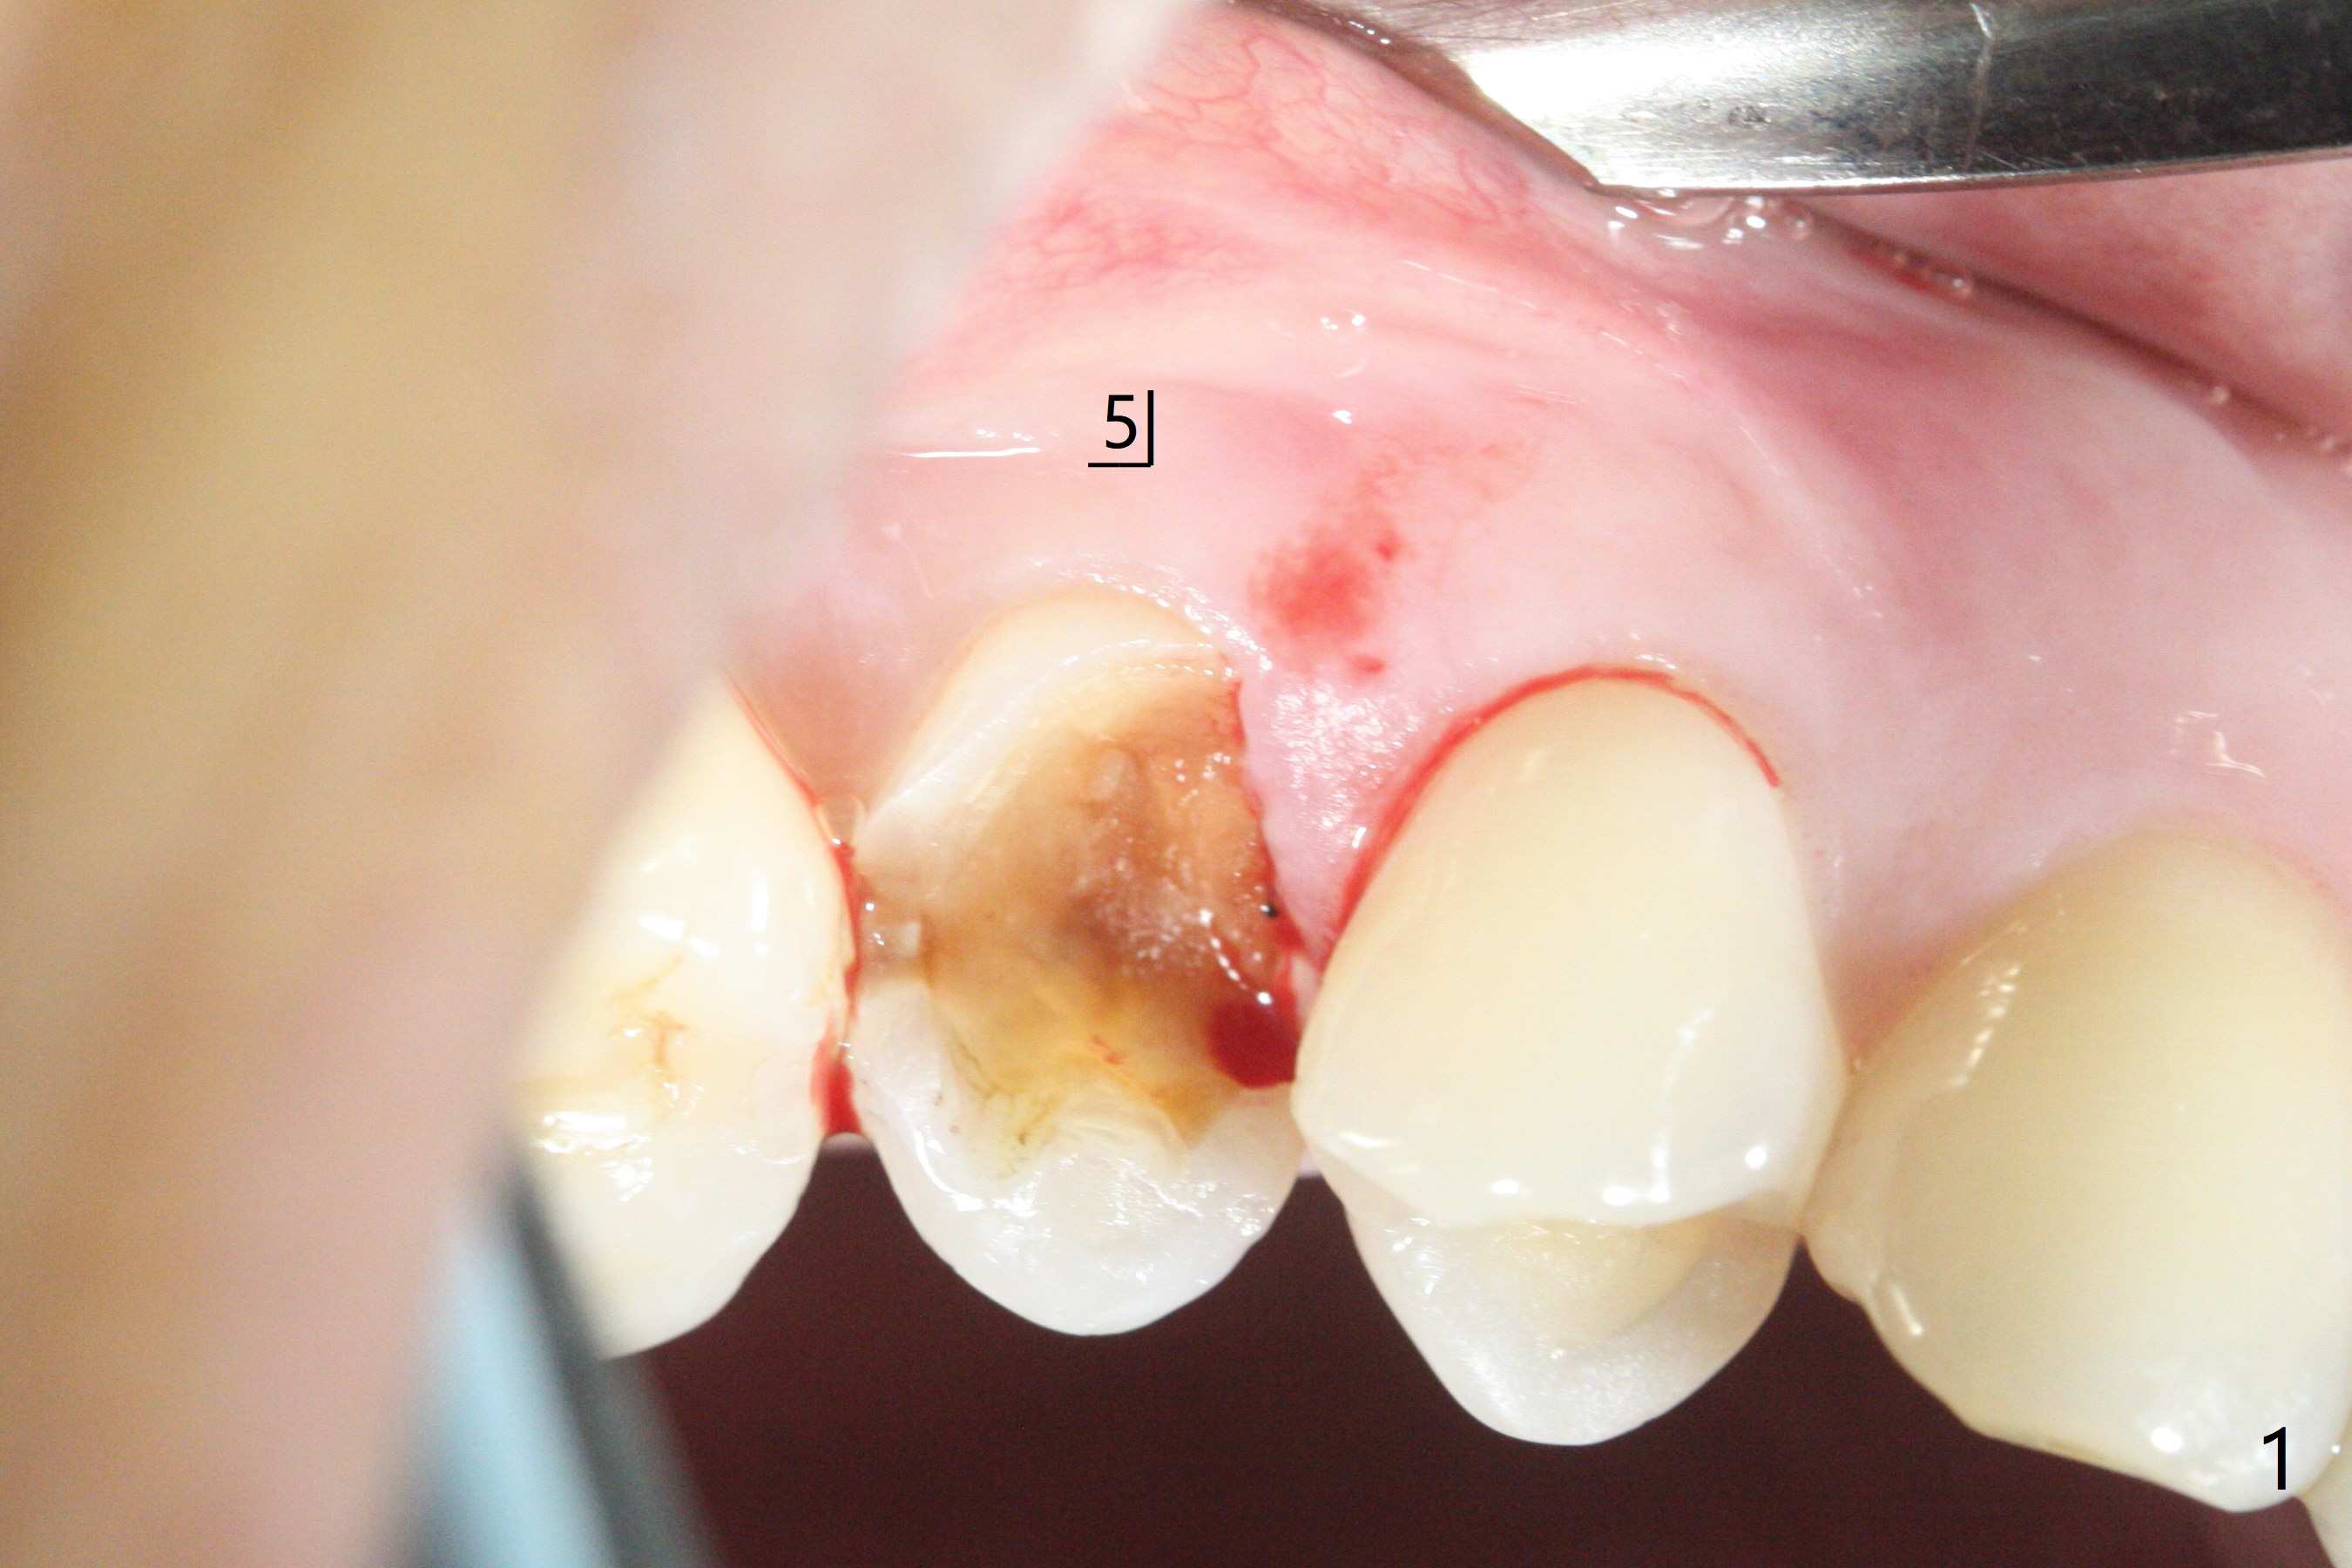

40岁女右上5近中龈下龋齿(图一),要求拔除植牙,上颌窦底板已经破坏穿孔,但是窦膜完整(图二)。清创后,放置PRF膜和粘性骨粉,用挖匙和上颌窦充填器尽量往上面推。然后放置导板,使用2.2x7.3 和3.0x7.3毫米钻头完成钻洞,可能无意中把骨粉推入上颌窦,之后利用报废植体(图三,四)完成提升,同时修补根尖缺损(利用之前放置的骨粉,图四:*,与图五(术前)对比)。当报废植体取出时,植牙窝已经形成,再放入少量骨粉,植入同样大小(之前扭力高)正式植体(不同品牌,图六,七),这时扭力低,放置愈合帽和骨粉(图七,八),以及6-9个月吸收膜,使用牙周胶水固定(图九),最后牙周敷料。术中术后几个小时没有上颌窦膜破裂迹象。术后一周牙周敷料松动,造成不适,去除时,膜好像粘附于敷料一起去除,骨粉暴露(图十),使用树脂敷料固定。后者术后一个月去除,因为局部有臭味。术后4个月切开放置愈合基台(图十一),术后五个月放置修复基台(图十二),使用塑料袖取模。术后5.5月同时放置牙冠和基台,十分顺手,口内粘固,之后同时取出,除去多余粘固剂,然后拧紧30Ncm(厂家推荐35 Ncm),一切非常顺利,觉得拍摄X光片是多余的。美中不足的是开孔(access hole)偏腭侧(图十二;由于自由手植入植体,与设计对比)。